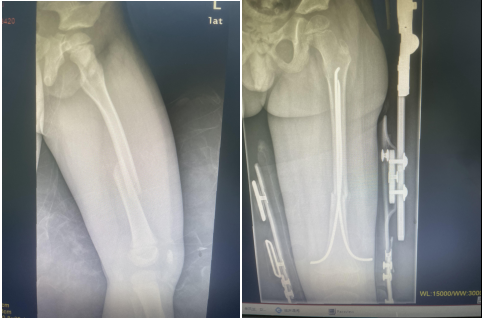

弹性髓内钉技术的特点:

①闭合整复骨折;

②保护了骨折周围的软组织附着和血运,骨折愈合快;

③利用其弹性和双“C”形的固定模式形成髓内支架,骨干周围的肌肉构成软组织框架,达到相对稳定的生物学固定;

④不损伤长骨干两端的骺板;

因此,该技术是一种微创、安全、有效、并发症少的内固定方法,适用于儿童长骨干横形、斜形及短螺旋形骨折,对肱骨和股骨近、远端干骺端骨折及桡骨颈骨折如应用得当也可获得满意的治疗效果。目前,弹性髓内钉技术在国内外已成为儿童四肢长骨干闭合性骨折治疗的首选方法。